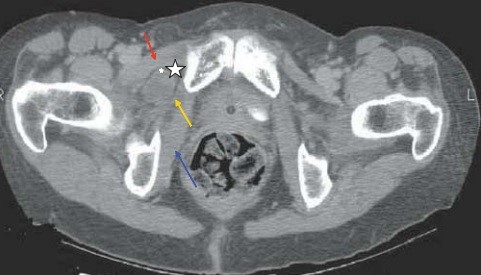

Chụp CT scan đa lát cắt trong cấp cứu có thể nhanh chóng chẩn đoán và can thiệp phẫu thuật sớm đối với các trường hợp thoát vị bịt do đó nâng cao được kết quả điều trị. Sử dụng CT scan trong chẩn đoán thoát vị bịt được báo cáo lần đầu tiên bởi Meziane và cộng sự vào năm 1983 [5].  Dấu hiệu trên CT scan hay gặp là quai ruột chui qua lỗ bịt nằm giữa cơ lược và cơ bịt ngoài.

thoatvi5

Hình 5: CTscan mặt phẳng axial cho thấy 1 quai ruột non trong túi thoát vị (hình ngôi sao trắng), ngoài cơ bịt ngoài (mũi tên vàng), trong cơ lược (mũi tên đỏ). Mũi tên xanh chỉ cơ bịt trong. * Nguồn: theo Sotiropoulos G.C (2013) [6]

Các dấu hiệu khác trên CT scan: các quai ruột non giãn, có hình mức dịch-khí, điểm chuyển tiếp ở lỗ bịt  Nếu chẩn đoán muộn có thể thấy các biến chứng thiếu máu, hoại tử hoặc thủng quai ruột. Có thể thấy dịch tự do ổ bụng, giữa các quai ruột, khí ổ bụng (trường hợp có biến chứng). Sử dụng CT scan giúp chúng ta có thể chẩn đoán thoát vị bịt trước mổ 43%-90% các trường hợp [4]. CT scan có thể chẩn đoán chính xác không chỉ thoát vị bịt mà còn chẩn đoán chính xác các tình trạng tắc ruột khác. Giải phẫu vùng thấp của tiểu khung nơi có lỗ bịt được bộc lộ rất tốt trên CT scan có độ phân giải cao. CT scan đa dãy với tái tạo đa bình diện cho các chi tiết giải phẫu chính xác, phân biệt thoát vị với các khối khác [u, tụ máu, áp xe]